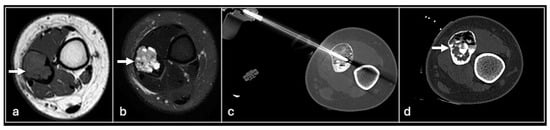

Figure 12. STIR axial (a), coronal (b) showing chondroblastoma in the humeral head (arrow) treated with CT-guided cryotherapy (c,d).

Cryoablation is the direct rapid cooling of lesions to temperatures as low as −100 °C to induce crystallisation of intracellular water thus causing apoptosis. This is achieved using rapidly expanding gas (usually argon) to cause a rapid drop in temperature via a phenomenon termed the Joule–Thompson effect [50]. Multiple freeze–thaw cycles are usually required with the latter achieved using helium gas infusion (Figure 12).

Indications are more wide-ranging than other forms of ablation. Curative oncological indications include benign desmoid tumours, osteoid osteomas, vascular malformations, aneurysmal bone cysts and neuromas [50,51]. Malignant lesions such as bone metastases can be treated curatively but palliation of painful bone metastases is a more established process [52,53,54].

Like other thermoablation methods, cryoablation is achieved by percutaneously inserting probes into the lesion. Unlike RFA, multiple needles can be used allowing more flexibility in tumours of different geometry and coverage of a larger ablation area. However, the ablation process takes longer and is more expensive than other options. As well as general thermoablation risks to the skin and perilesional structures, specific risks include cryomyositis (peritumoural muscle inflammation) and cryoshock (a systemic inflammatory response from the release of inflammatory mediators). Numerous methods can be employed to minimise inadvertent freezing risk such as hydrodissection and active or passive warming of the adjacent structures [33,55]. Temperature monitoring and direct visualisation of the ice ball using CT or ultrasound during cryotherapy can also reduce the risk of injuring adjacent structures [56,57].